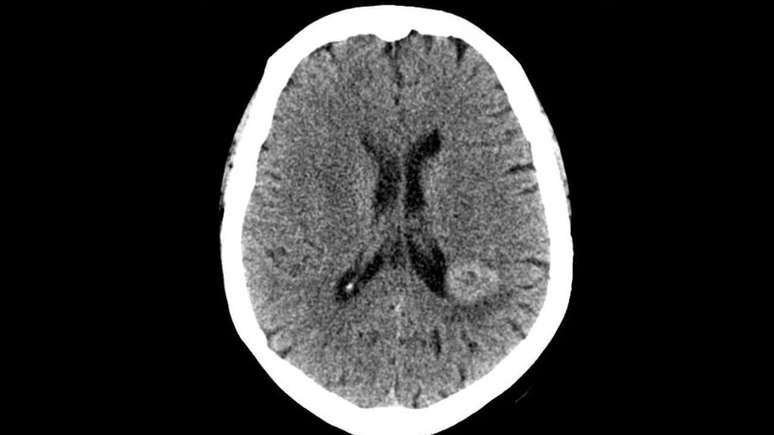

First, it all started when a middle-aged patient, with no psychiatric history, started hearing unknown and persistent voices. They asked her to see a doctor and undergo a brain examination, because they calmly stated that she had a tumor there.

When he told the experts, he received no attention. Therefore, they did not want her to perform any tests. However, the rumors continued, attesting that the investigation of the case was urgent. So the doctors accepted the proposal to reassure her. And the result was shocking. They discovered that he actually had a meningioma, located exactly in the spot they indicated.

Having said that, they scheduled the surgery, which was a success, and then the most amazing thing happened. When the woman woke up from the procedure, she heard voices telling her: “We are happy to have been able to help you. Goodbye”. And they haven’t appeared since.